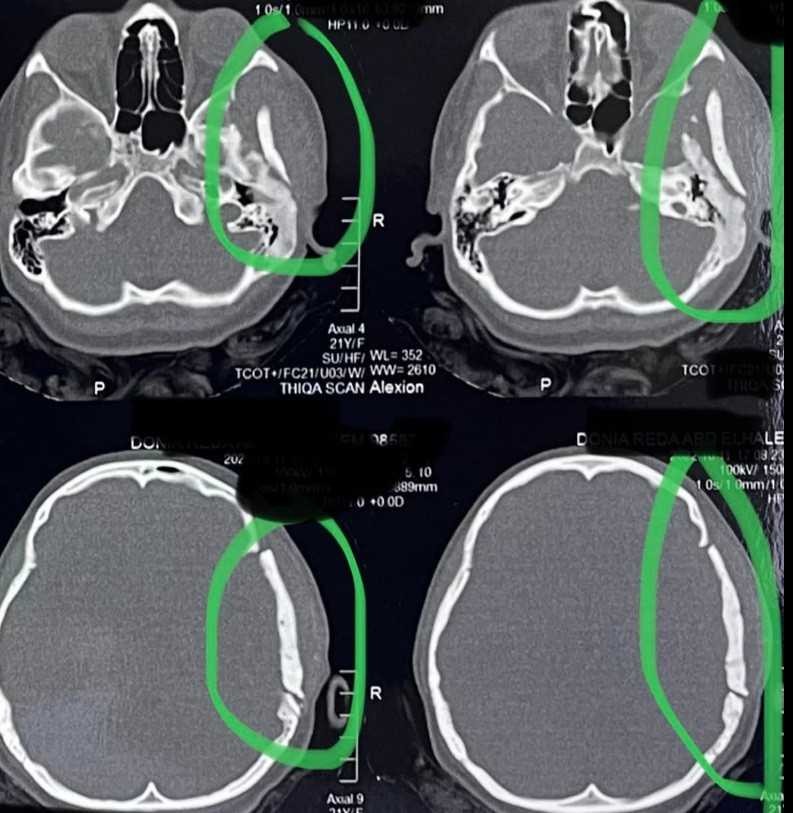

A 21-year-old female suffering from bone fibrous dysplasia was diagnosed and treated. This disease is characterized by the growth of benign bone tumors in multiple body areas, which can affect motor function and cause chronic pain.

• Accurate diagnosis using advanced imaging

• Periodic imaging follow-up